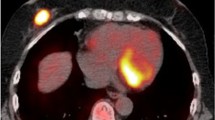

The aim of this study was to determine if functional parameters extracted from the hybrid positron emission tomography/magnetic resonance imaging (PET/MRI) correlate with the immunohistochemical markers of breast cancer (BC) lesions, to assess their ability to predict BC subtype.

This prospective study was approved by the institution’s Ethics Committee, and all patients provided written informed consent. A total of 50 BC patients at diagnosis underwent PET/MRI before pharmacological and surgical treatment. For each primary lesion, the following data were extracted: morphological data including tumour-node-metastasis stage and lesion size; apparent diffusion coefficient (ADC); perfusion data including forward volume transfer constant (Ktrans), reverse efflux volume transfer constant (Kep) and extravascular extracellular space volume (Ve); and metabolic data including standardized uptake value (SUV), lean body mass (SUL), metabolic tumour volume and total lesion glycolysis. Immunohistochemical reports were used to determine receptor status (oestrogen, progesterone, and human epidermal growth factor receptor 2), cellular differentiation status (grade), and proliferation index (Ki67) of the tumour lesions. Correlation studies (Mann–Whitney U test and Spearman’s test), receiver operating characteristic (ROC) curve analysis, and multivariate analysis were performed.